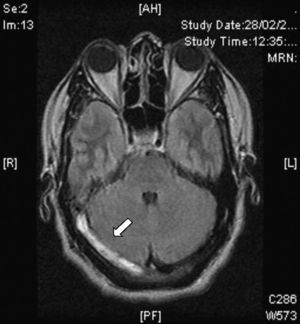

Signo delta o del triángulo vacío. Se observa después de la administración de medio de contraste y se forma por un defecto de llenado intraluminal rodeado por contraste en la porción posterior del SSS. Se presenta hasta en un 30% de los casos (fig. 3).

Resonancia magnéticaEn la actualidad el diagnóstico de TVC se confirma con IRM combinada con venorresonancia. La IRM tiene una sensibilidad más elevada para detectar las alteraciones del parénquima cerebral, formación de trombos, hemorragias petequiales y flujo sanguíneo31. El protocolo de estudio incluye secuencias T1 (con y sin contraste), T2, FLAIR, difusión y venografía27 (fig. 4). De acuerdo a la evolución de la TVC el coágulo puede tomar diferentes aspectos, por ejemplo, en etapas muy tempranas o agudas (< 5 días), los vasos ocluidos aparecen isointensos en secuencias en eco de espín ponderadas en T1 e hipointensos en T2. A partir del día 5 y hasta el día 35 la oxihemoglobina del trombo se convierte gradualmente en metahemoglobina y podemos observar imágenes hiperintensas en T1 y en T232. En etapas tardías o crónicas el patrón de presentación en IRM es más variable. El seno venoso trombosado puede recanalizarse o permanecer ocluido de forma parcial o completa, lo que puede ser interpretado como TVC recurrente. Por lo anterior, la venorresonancia (fig. 5) y la TC helicoidal están indicadas en las etapas tempranas menores a 5 días y en las etapas tardías (> 6 semanas), períodos en los que la IRM puede mostrar falsos negativos. A los 6 meses las anormalidades en los estudios de imagen persisten en aproximadamente dos tercios de los pacientes. Los falsos positivos se deben a un flujo sanguíneo venoso lento sin trombosis. Las secuencias de venorresonancia incluyen: TOF (time of flight) y contraste de fase. Las de contraste de fase son de adquisición rápida y permiten analizar tanto la dirección del flujo como su cuantificación en la vasculatura obstruida33.